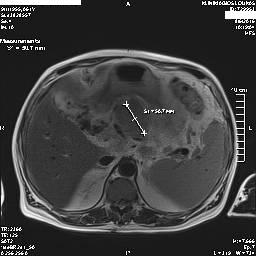

Στα πλαίσια διερεύνησης του πρωτοεμφανιζόμενου διαβήτη, υποβλήθηκε σε μαγνητική τομογραφία άνω κοιλίας (MRI/MRCP) που ανέδειξε μια συμπαγή μάζα στην κεφαλή του παγκρέατος, διαμέτρου περίπου 2εκ και μεγάλη διάταση του παγκρεατικού πόρου.

Ο ασθενής υποβλήθηκε σε ενδοσκοπικό υπέρηχο που έδειξε μια υποηχοϊκή μάζα διαμέτρου 21 χιλιοστών, με σαφή όρια, στην παγκρεατική κεφαλή και μεγάλη διάταση του χοληδόχου πόρου και του παγκρεατικού πόρου (διάμετρος 12 χιλιοστά).

Μάζα παγκρέατος στη μαγνητική τομογραφία